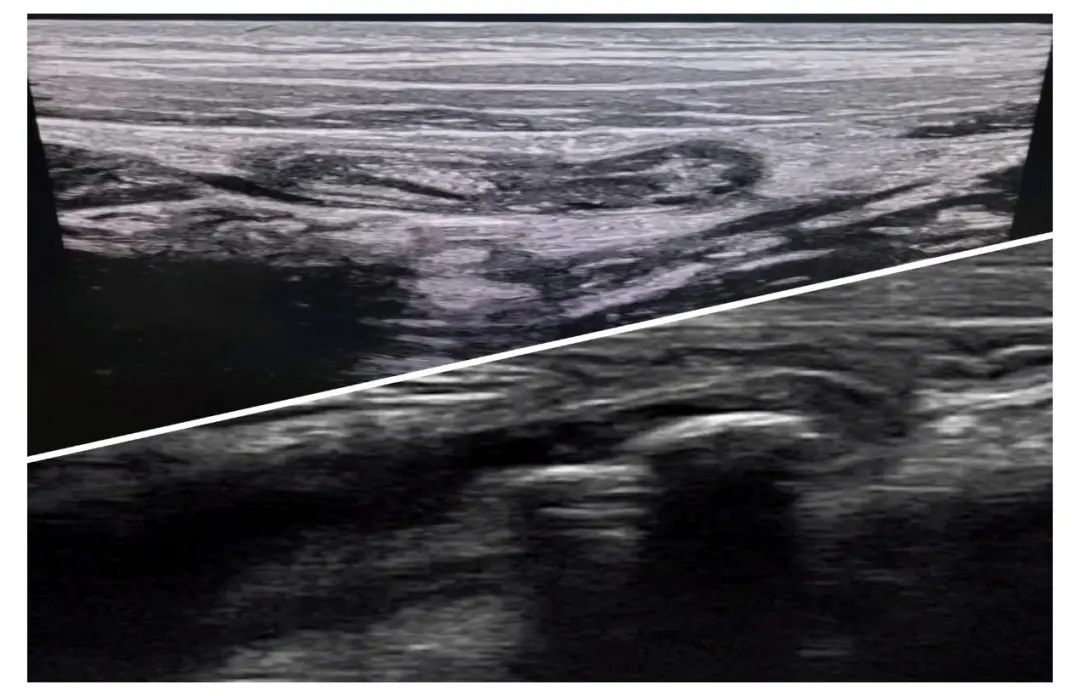

闌尾炎的超聲診斷要點(diǎn)

1.通常以直徑大于6mm,7mm做為診斷闌尾炎的閾值。

2.不可壓縮性。在最大壓痛點(diǎn)位置,可見同心分層、不可壓縮的臘腸樣結(jié)構(gòu),管腔內(nèi)可見透聲差的液體。

3.壁增厚或沒有明顯的壁增厚但管腔擴(kuò)張。正常闌尾壁厚度小于3mm出現(xiàn)高回聲的粘膜下層增厚是粘膜下層水腫的特征。

4闌尾壁層次。要觀察高回聲的黏膜下層,有完整的黏膜下層,并且呈進(jìn)行性腫大則提示化膿性闌尾炎,粘膜下層局部或全部消失則提示壞疽性闌尾炎。

5.周圍脂肪回聲增強(qiáng)。是闌尾炎發(fā)作6-12小時(shí)之后,炎性累及闌尾系膜脂肪所致。